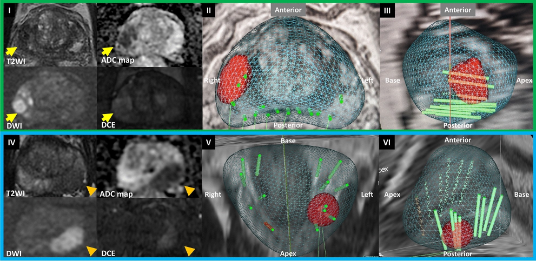

На сегодняшний день одним из наиболее информативных методов диагностики рака простаты является мультипараметрическое МРТ простаты. Аббревиатура современной классификации подозрительных участков простаты на МРТ называется PIRADS. В своем заключении МРТ простаты вы можете увидеть такое обозначение с последующим цифровым индексом от 2 до 5. Существует прямая корреляция между этой классификацией и риском рака простаты: у пациентов с PIRADS 2 вероятность рака простаты не превышает 4%, при PIRADS 3 — 13-21%, при PIRADS 4 — 38-55%, при PIRADS 5 — 73-78%. Современные протоколы диагностики рака простаты рекомендуют выполнение биопсии простаты при PIRADS 3, 4 и 5.

Стандартная биопсия простаты проводится под ультразвуковым контролем. Однако, к сожалению, на ультразвуковых изображениях не видны участки, подозрительные на рак. То есть нормальная ткань и рак выглядят одинаково, в связи с чем длительное время биопсия простаты заключалась в случайном заборе, в среднем, 12 фрагментов ткани простаты исходя из ранее разработанной схемы. Существенным минусом в диагностике локализованного рака простаты является вероятность ложноотрицательного результата. То есть рак у пациента есть, но стандартная случайная биопсия не позволила его выявить, так как фрагменты ткани простаты берутся по схеме, а не прицельно.

Недостаток такого случайного забора ткани простаты при биопсии заключается в вероятности того, что игла биопсийного пистолета пройдет мимо фокуса рака простаты, и результат гистологического исследования будет ложноотрицательным. Таким образом, стандартный метод биопсии простаты не позволяет «прицелиться» в те очаги, которые были выявлены на МРТ.

Технологическое развитие медицинского оборудования привело к возможности совмещения снимков МРТ и УЗИ; такая технология получила название «фьюжн». Это позволяет, при наложении друг на друга и синхронизации МРТ-изображения и ультразвукового изображения, произвести точечный забор материала из подозрительного фокуса, диагностированного на МРТ. Информативность такого исследования значительно превосходит информативность стандартной методики и снижает вероятность получения ложноотрицательных результатов.

Кроме точного выявления опухоли, фьюжн-биопсия простаты позволяет выявить тот самый агрессивный, клинически значимый рак простаты (Глисон 7 и более), что повлияет на выбор единственно правильной тактики лечения.